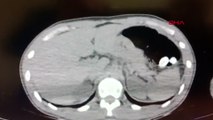

Konya’da, 12 yaşındaki kızın midesinden 2 kilo 850 gram ağırlığında 20 santim büyüklüğünde taş sertliğinde saç ve sakız yumağı çıkarıldı.